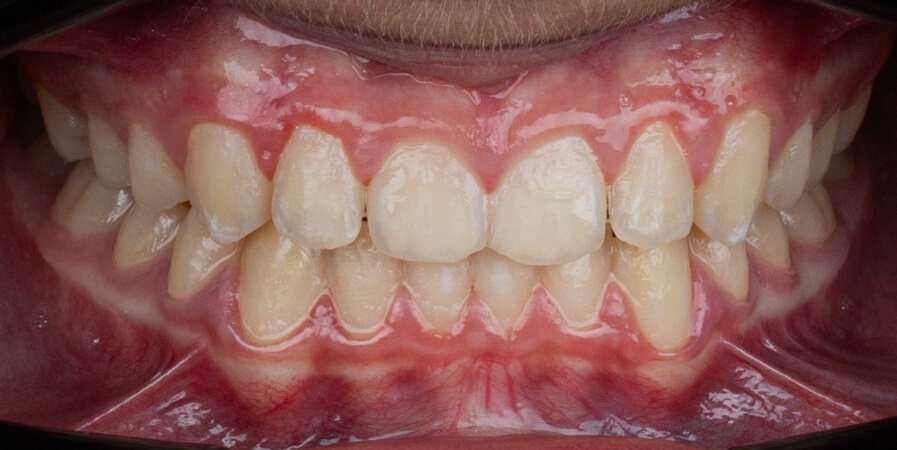

This case, led by Dr. Romina Vignolo Lobato, showcases the treatment of a 12-year-old female patient with a Class II malocclusion. Using the Angel Aligner Pro system with the A8 protocol and an asymmetric virtual jump, the treatment achieved crowding resolution, bite correction, and improved facial profile in just 11 months with 30 aligners. The minimally invasive approach combined efficiency with precise control, delivering both functional and aesthetic results.